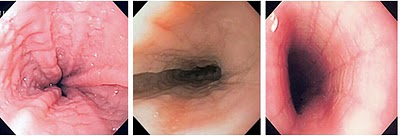

| O esôfago é a porção do tubo digestivo que faz comunicar a garganta (faringe) com o estômago. Possui duas faixas musculares (esfíncteres), assim distribuídas: 1ª que liga a garganta ao esôfago e a 2ª que liga o esôfago ao estômago (também conhecido como Cardia). Estes músculos quando em relaxamento permitem a passagem de alimentos, líquidos,.... Diversas são as patologias que acometem o esôfago, entre elas: Varizes de esôfago, Hérnia de hiato, Doença do Refluxo Gastroesofágico, Câncer de esôfago, Esôfago de Barret, ...